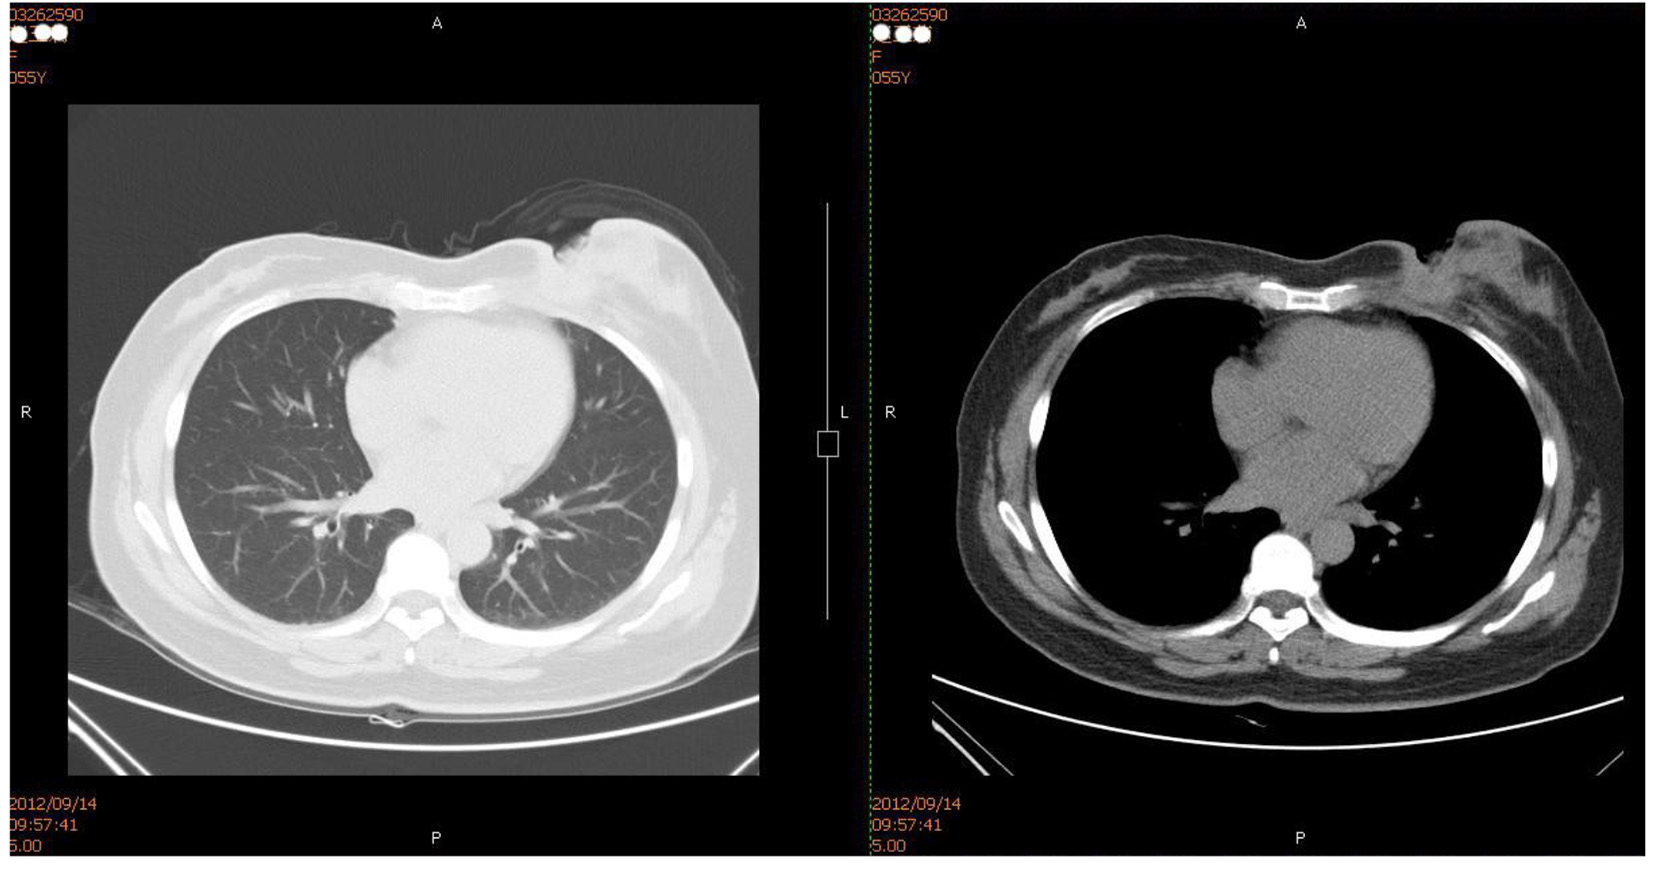

On August 20, 2012, the patient was hospitalized again for 1 month due to ulceration of the left breast. On physical examination, an approximately 7 × 6 cm neoplasm was palpable in the left internal mammary area and fixed on the chest wall. The skin ulceration was found in the central area with about 5 × 3.5 cm anabrosis, deep up to the pectoralis, the surface of which was covered by yellow pus embryo; an approximately 2 × 1 cm swollen lymph node was palpable in the left armpit. Chest CT showed the possibility of local recurrence or metastasis (Fig. 1). Biopsy pathology of the anabrosis showed cancer infiltration. Core needle pathology of axillary lymph nodes showed cancerometastasis. The pus embryo bacteria at the anabrosis were cultured into Pseudomonas aeruginosa. No metastasis signs were seen by SPECT-bone scan.

Figure 1.

Click for large image

Figure 1. Chest CT (on Setpember 14, 2012): local soft tissues of the left breast were absent and the local skin incrassation was obvious. Subcutaneous irregular soft tissue density image was seen, the border of which with the residual mammary tissue was unclear and stretched inwards the muscle tissues and costal cartilages without definite damage in local rib sclerotin.